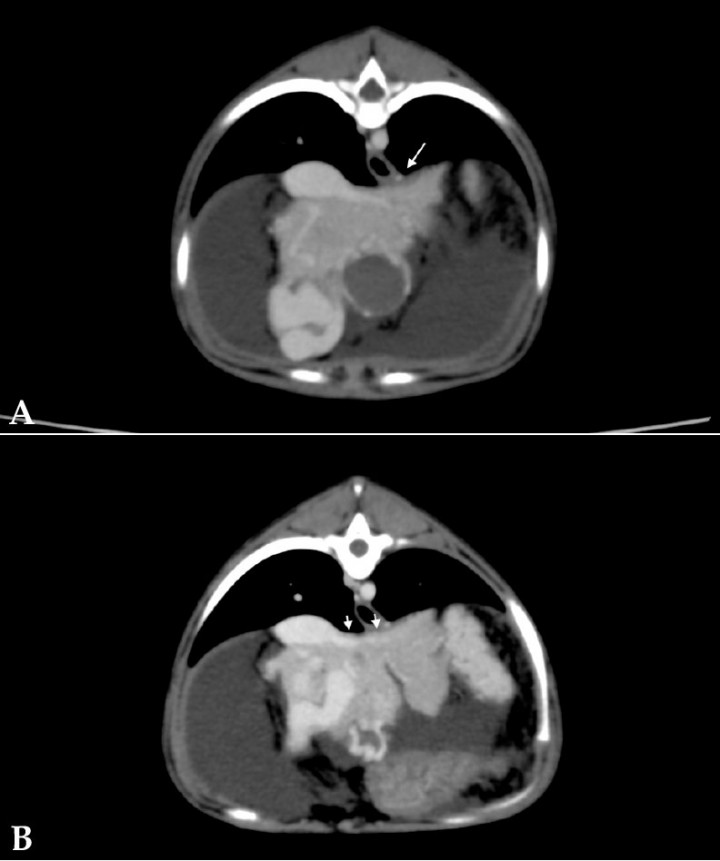

A partir de las ramas de la arteria hepática principal se observó un plexo de vasos tortuosos que desembocaban en dos ramas portales: en una rama intrahepática en el lóbulo medial izquierdo, craneoventral y adyacente al diafragma, resultando en una rama portal anormalmente dilatada y tortuosa (Fig. 7A); y en la propia rama portal tortuosa y aumentada de tamaño a partir de dos arteriolas hepáticas que nacían desde el lado derecho de la arteria hepática (Fig. 7B).

<p>Imágenes de tomografía computarizada transversales tras la administración de contraste intravenoso, ventana de tejido blando. (<strong>A</strong>) Se observa la rama portal intrahepática en lóbulo medial izquierdo anormalmente dilatada y tortuosa (flechas). (<strong>B</strong>) Se aprecian vasos tortuosos (flechas) que drenan en la vena porta tortuosa y aumentada de tamaño.</p>

Imágenes de tomografía computarizada transversales tras la administración de contraste intravenoso, ventana de tejido blando. (A) Se observa la rama portal intrahepática en lóbulo medial izquierdo anormalmente dilatada y tortuosa (flechas). (B) Se aprecian vasos tortuosos (flechas) que drenan en la vena porta tortuosa y aumentada de tamaño.